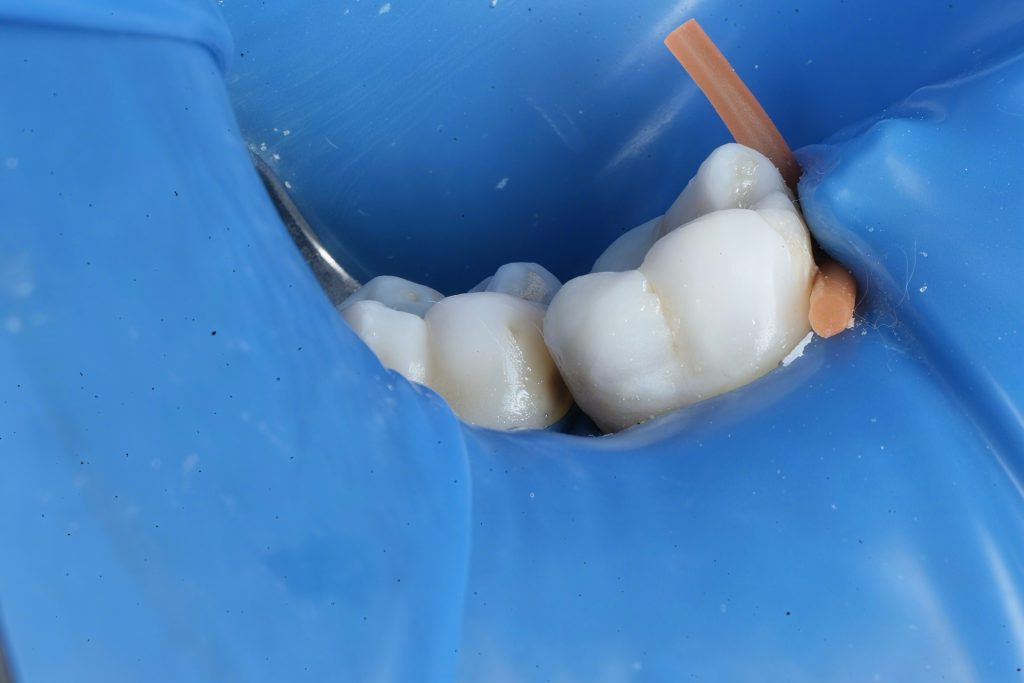

2️⃣ Isolation & Access

Rubber dam isolation was achieved to prevent contamination (Fig 2). Conservative access cavity preparation was performed under a dental microscope to maintain structural integrity and preserve pericervical dentin.

- Fig 2: Rubber dam isolation for aseptic workflow.

- Fig 6: Class II build-up using Garrison matrix + GC EverX Flow.